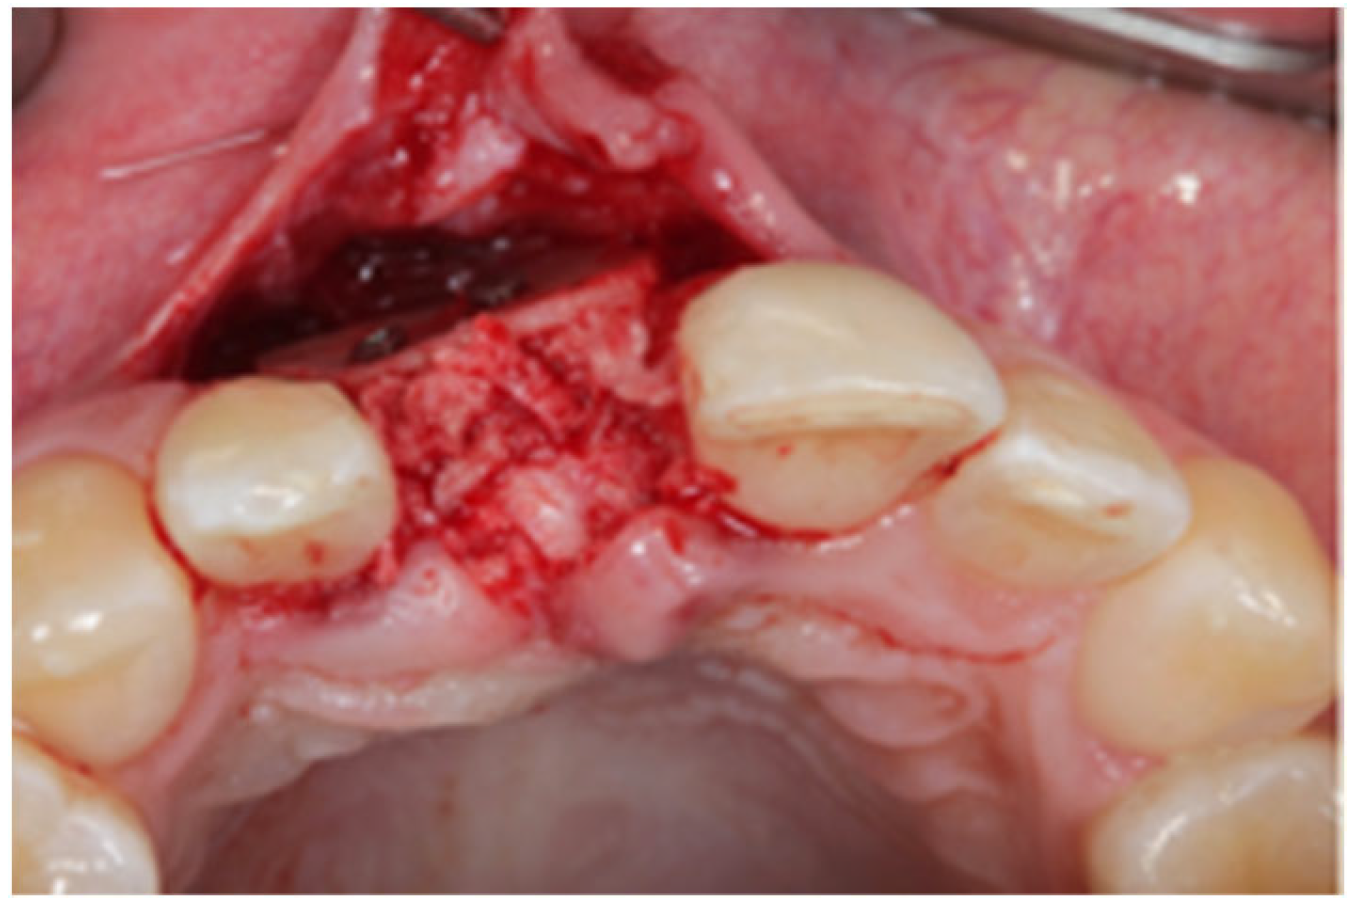

2.1. Surgical Technique